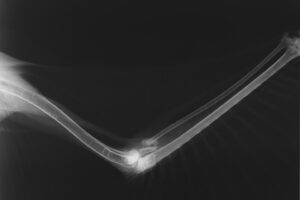

早速レントゲン検査を行ったところ、左翼の橈骨(とうこつ)と尺骨を骨折し、肘を脱臼している事がわかりました。全身麻酔をかけて関節の状態を検査したところ、幸い重要な腱や筋肉に大きな損傷はありませんでしたが、骨折した骨がすでに不整癒合しかけていました。その状況から、今回は手術によって外科的に整復する事を避け、運動制限とリハビリテーションで飛翔力の回復を試みることにしました。